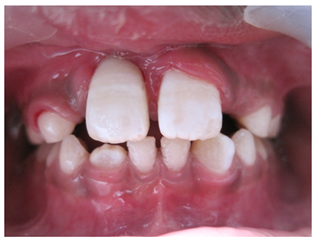

A 10year old boy reported to the department of Pedodontics with a chief complaint of missing upper front tooth and gave a history of fall from bike while 5 days back. They had been to pediatrician for the lacerated lip and got it sutured. Parents had kept the avulsed tooth in paper without knowledge of reimplantation of the same tooth. Patient had no relevant medical and family history. On examination swelling and suture was present on upper lip, lacerated gingiva with healing socket in 11 regions. 21 was intact, vital and non mobile. (Figure 1) (Figure 2) On examination of avulsed tooth 11, it was found to have open apex (Figure 3). On intraoral radiographic examination, no fracture was seen with alveolar bone (Figure 4). Thus avulsed tooth was cleaned and debrided with soft pumice prophylaxis, gentle scaling was done to remove ligament remnants. It was then placed in 1.23% sodium fluoride for 15minutes. Extraoral endodontic therapy was also done using retrograde filling of MTA (Figure 5). Local anesthesia was administered and socket was cleaned, curetted and irrigated to remove clot and debris and 11 was slowly reimplanted in socket. Orthodontic wire – composite splinting was done for 4weeks as the dry storage was more than 60minutes (Figure 6). Systemic antibiotics amoxicillin and doxycycline were prescribed for 5days. The patient was recalled after 1 month and splint was removed. No mobility was present. Again patient was recalled after 2months to check the condition (Figure 7). Again patient was recalled after 6months; tooth had slightly discolored but was not mobile and maintained the space (Figure 8). Patient was happy and contended with the reimplantation of his own tooth without disturbing his original look.

Figure 7 Two months postoperative photograph.